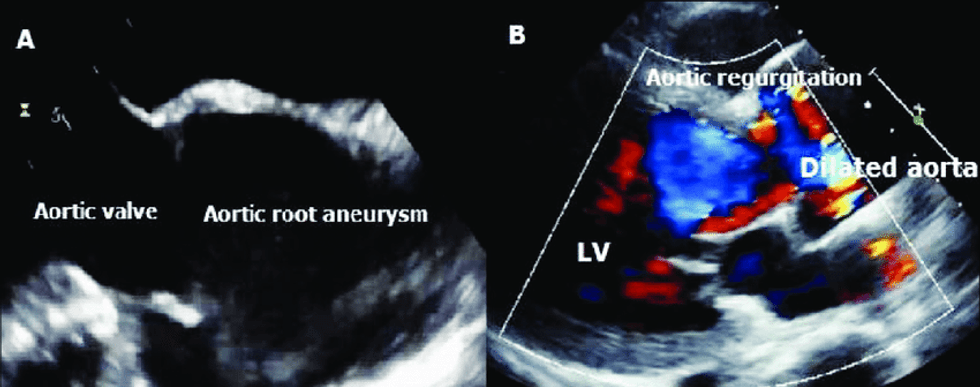

Anatomikisht, valvula e aortës përbëhet nga tri fletëza gjysmëhënore: koronare të majtë, koronare të djathtë dhe jo-koronare. Nëse gjaku kthehet, quhet regurgitim dhe shkaktohet nga dobësia e valvulës, e cila quhet insuficiencë. Insuficienca më së shpeshti shfaqet si pasojë e keqformimeve të kushtëzuara gjenetikisht, të ashtuquajturat valvula aortike bicuspid, kur në vend të tri normale, valvula aortike përbëhet nga dy fletë, transmeton Telegrafi.

Shfaqja e një valvule aortale bikuspidale shoqërohet me rritje të rrezikut të komplikimeve kardiovaskulare, përfshirë endokarditin infektiv. Nëse paraqitet insuficienca akute e aortës, është indikacion për kirurgji urgjente në zemër.

Stenoza e aortës ndodh si rezultat i rrjedhjes së turbullt të gjakut nëpër vrimën e aortës, e cila çon në ndryshime degjenerative që rezultojnë në funksion të pamjaftueshëm të valvulës. Stenoza paraqet një pengesë mekanike për qarkullimin normal të gjakut, prandaj, nëse zgjat më shumë, mund të çojë në trashje të muskujve të zemrës dhe/ose zgjerim (zgjerim) të pjesës fillestare të aortës.

Zgjerimi poststenotik i aortës është një zgjerim i diametrit të aortës ascendente, i cili supozohet se shkaktohet nga rritja e shpejtësisë së rrjedhës nëpër grykën e aortës, si dhe rrjedha e turbullt e gjakut që ndikon në stresin tangjencial të prerjes së murit të aortës, duke shkaktuar rrallimin dhe zgjerimin e tij.